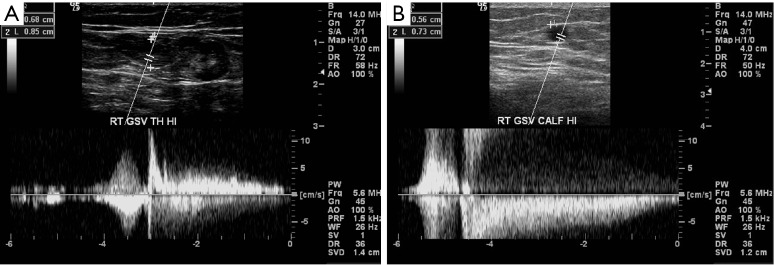

Figure 3.

Spectral Doppler evaluation shows persistent retrograde flow beyond 0.5 second in the great saphenous vein suggestive of venous reflux. Retrograde flow can be seen up-to 3 seconds in (A) and 4 seconds in (B).